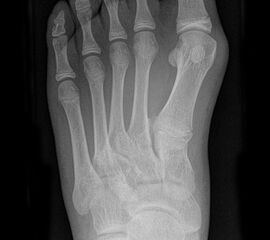

Die folgenden Bilder zeigen die belastete Röntgenaufnahmen des linken Fußes einer jungen Patientin zu Beginn der Therapie und nach 6 Monaten Training. Erkennbar ist die höhere muskuläre Verspannung des Fußes mit verbesserter Stellung der milden Hallux valgus Deformität.